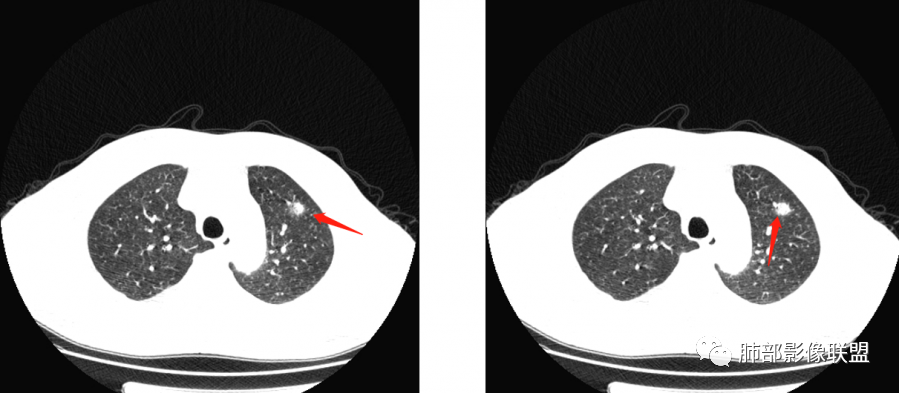

南边:

边界模糊,距离胸膜有间隙,内部支气管通畅

一月后:

病灶此起彼伏